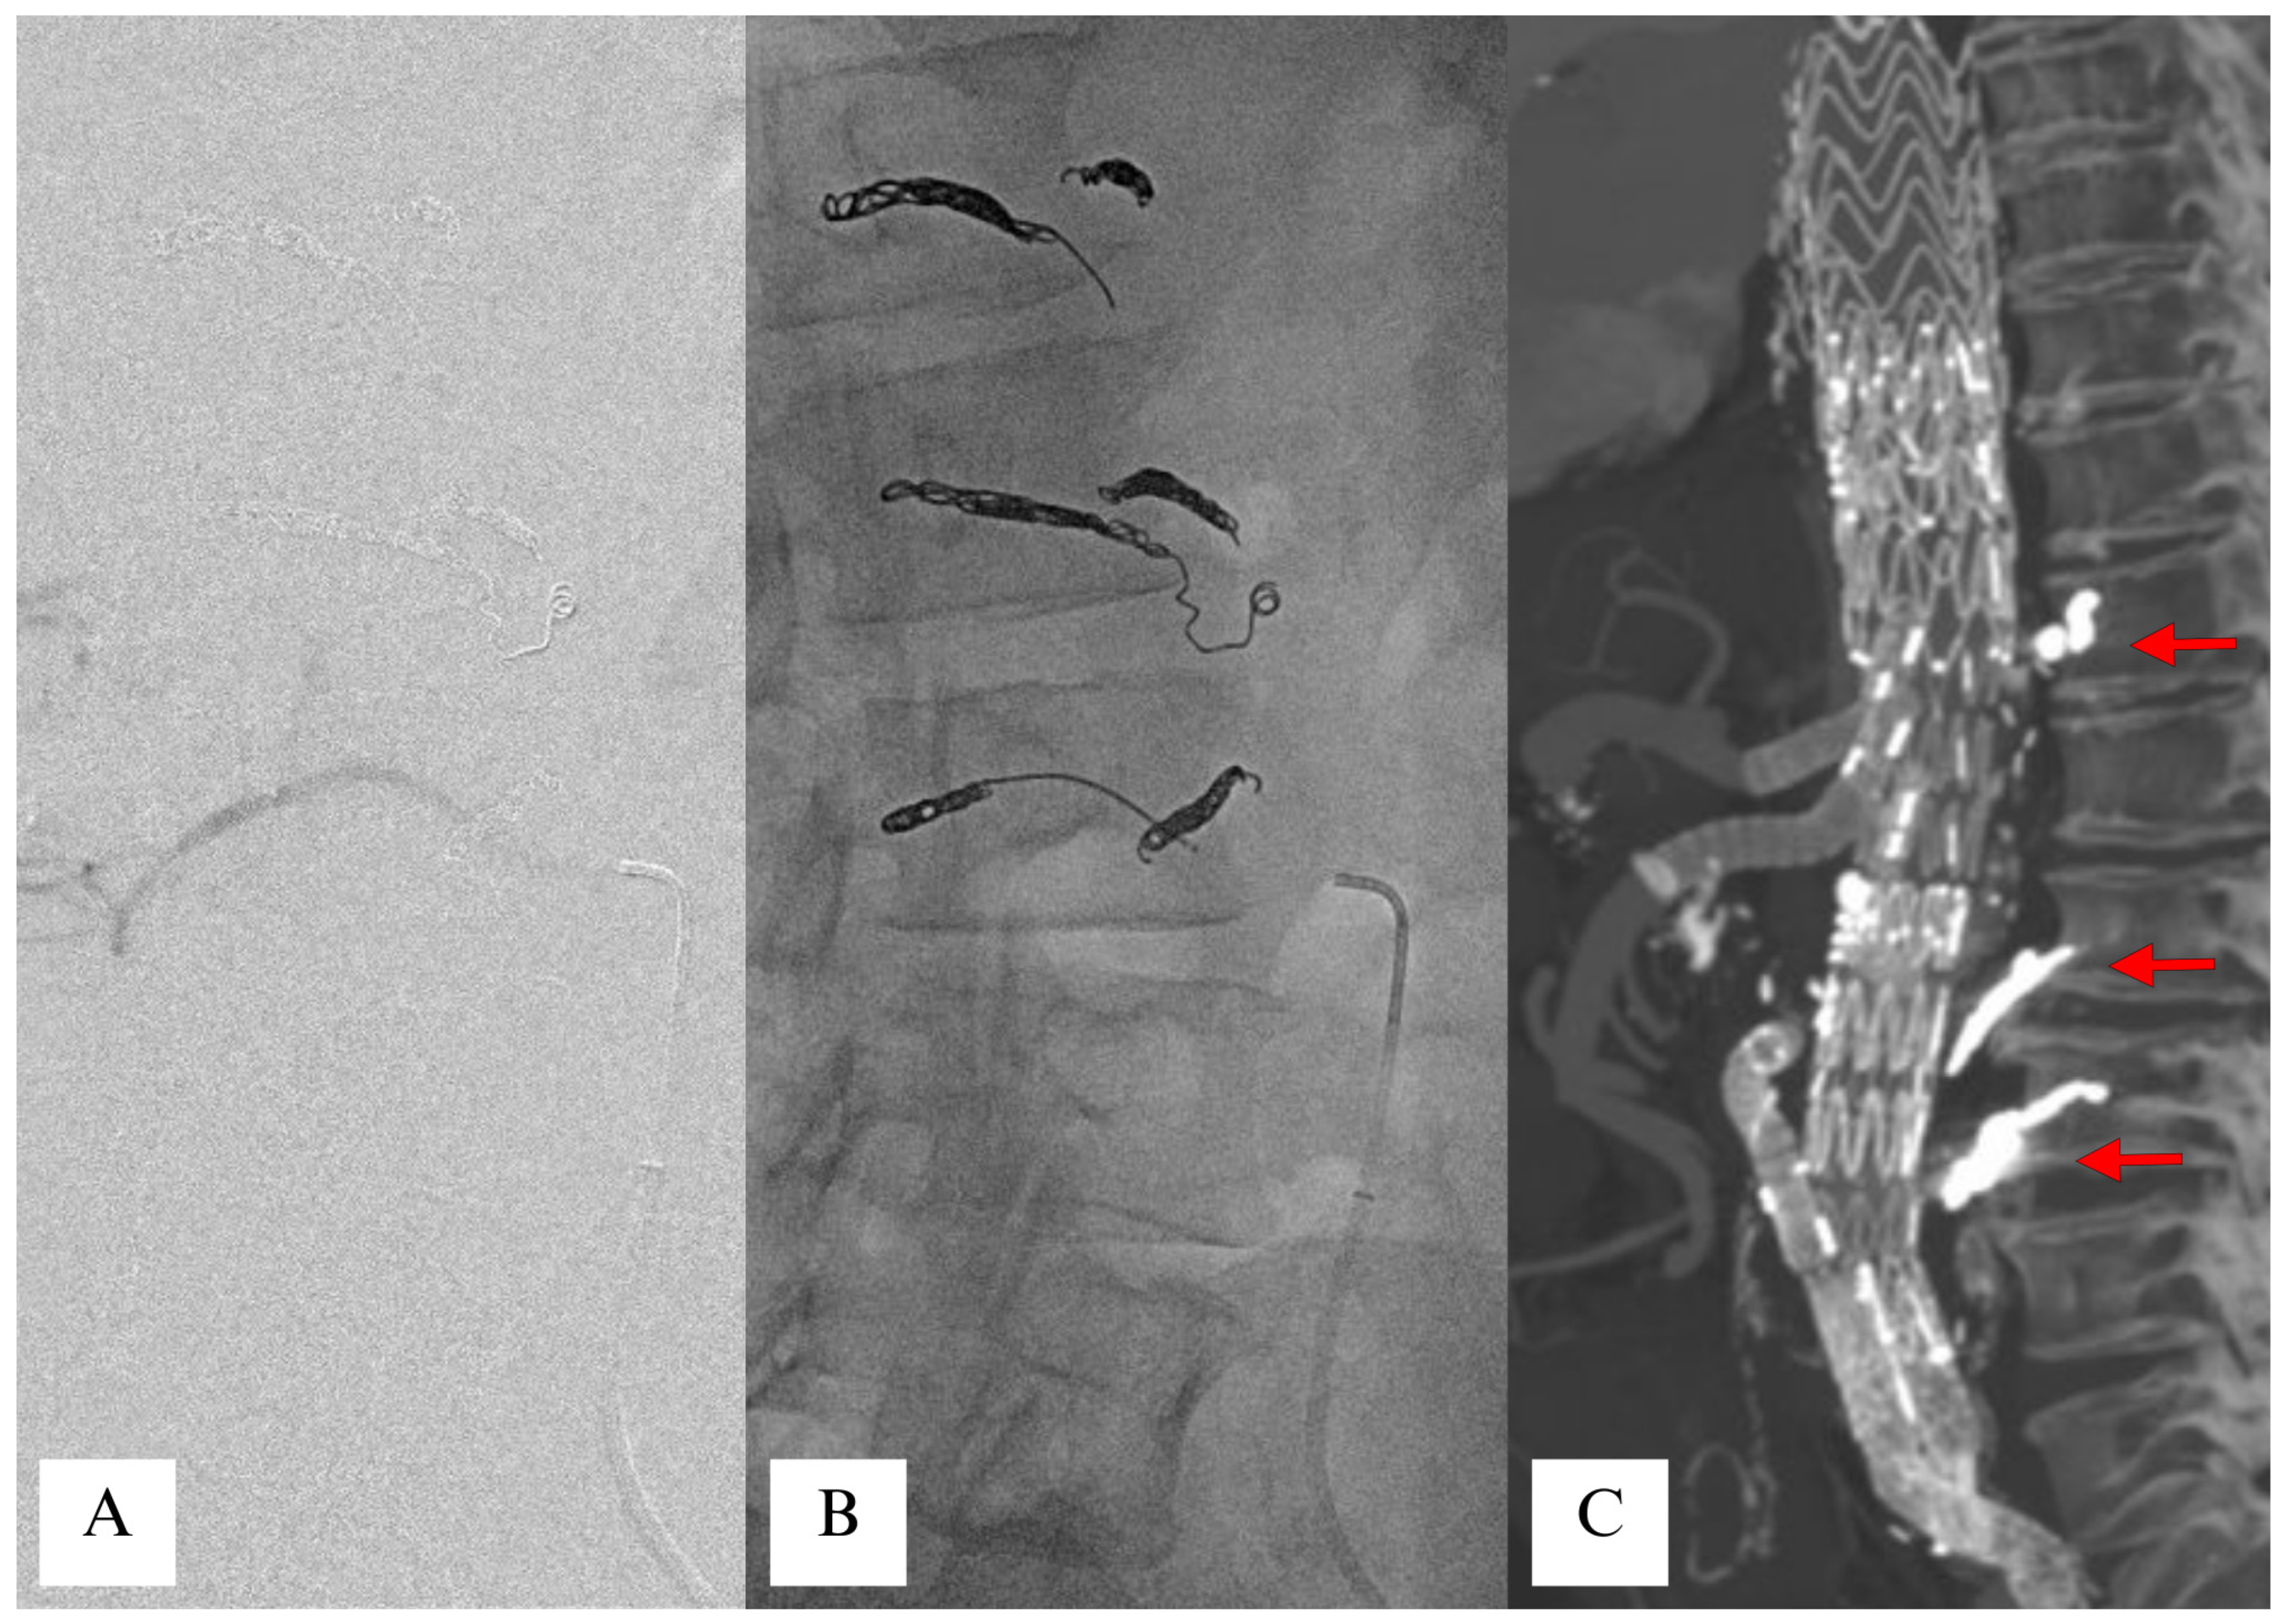

3.1.3. Selective Coil Embolization of Segmental Arteries (MIS2ACE)

- Etz, C.D.; Debus, E.S.; Mohr, F.W.; Kölbel, T. First-in-man endovascular preconditioning of the paraspinal collateral network by segmental artery coil embolization to prevent ischemic spinal cord injury. J. Thorac. Cardiovasc. Surg. 2015, 149, 1074–1079. [Google Scholar] [CrossRef] [PubMed]

- Branzan, D.; Etz, C.D.; Moche, M.; Von Aspern, K.; Staab, H.; Fuchs, J.; Bergh, F.T.; Scheinert, D.; Schmidt, A. Ischaemic preconditioning of the spinal cord to prevent spinal cord ischaemia during endovascular repair of thoracoabdominal aortic aneurysm: First clinical experience. EuroIntervention 2018, 14, 828–835. [Google Scholar] [CrossRef]

- Addas, J.A.K.; Mafeld, S.; Mahmood, D.N.; Sidhu, A.; Ouzounian, M.; Lindsay, T.F.; Tan, K.T. Minimally Invasive Segmental Artery Coil Embolization (MISACE) Prior to Endovascular Thoracoabdominal Aortic Aneurysm Repair. Cardiovasc. Interv. Radiol. 2022, 45, 1462–1469. [Google Scholar] [CrossRef]

- Haunschild, J.; Köbel, T.; Misfeld, M.; Etz, C.D. Minimally invasive staged segmental artery coil embolization (MIS2ACE) for spinal cord protection. Ann. Cardiothorac. Surg. 2023, 12, 492–499. [Google Scholar] [CrossRef]

- Dabravolskaite, V.; Xourgia, E.; Kotelis, D.; Makaloski, V. The Safety and Outcome of Minimally Invasive Staged Segmental Artery Coil Embolization (MIS2ACE) Prior Thoracoabdominal Aortic Aneurysm Repair: A Single-Center Study, Systematic Review, and Meta-Analysis. J. Clin. Med. 2024, 13, 1408. [Google Scholar] [CrossRef] [PubMed]

- Branzan, D.; Geisler, A.; Steiner, S.; Scheinert, D.; Funk, K.; Schmidt, A. Endovascular occlusion of segmental arteries feeding the anterior spinal artery to stage endovascular thoracoabdominal aortic repair. JTCVS Open 2024, 18, 1–8. [Google Scholar] [CrossRef] [PubMed]